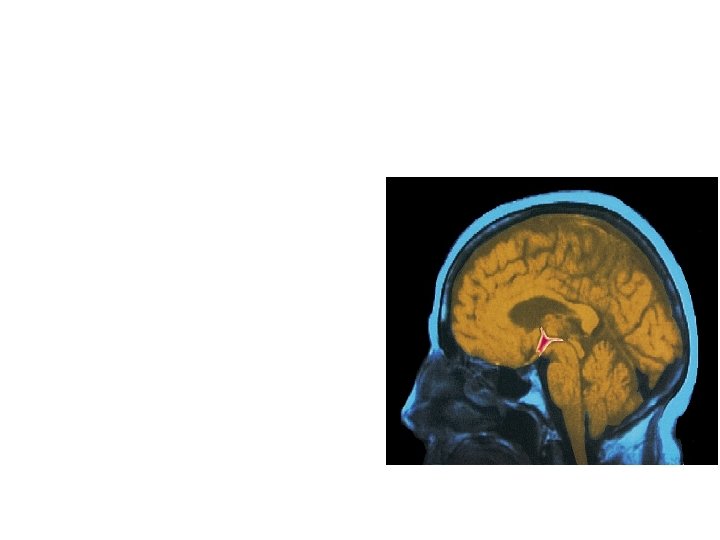

Parts of the Brain THALAMUS Relays messages amygdala hippocampus pituitary CEREBELLUM Coordination and balance BRAINSTEM Heart rate and breathing

The Limbic System • Hypothalamus, pituitary, amygdala, and hippocampus all deal with basic drives, emotions, and memory • Hippocampus Memory processing • Amygdala Aggression (fight) and fear (flight) • Hypothalamus Hunger, thirst, body temperature, pleasure; regulates pituitary gland (hormones)

The Brain • Thalamus – the brain’s sensory switchboard, located on top of the brainstem – it directs messages to the sensory receiving areas in the cortex and transmits replies to the cerebellum and medulla